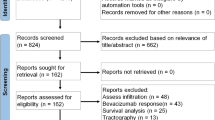

Diffusion-weighted images (DWIs) were acquired in twenty-three patients following surgery, prior chemoradiation and within 7 days following completion of treatment, using b-values ranging from 0 to 5000s/mm2. Mono-exponential diffusion (apparent diffusion coefficient: ADC), isotropic (non-directional) DKI model with apparent diffusivity (Dapp) and kurtosis (Kapp) estimates as well as SE model with distributed-diffusion coefficient (DDC) and mean intra-voxel heterogeneity (α) were computed for all patients prior and after chemoradiation. Median values were calculated for normal appearing white matter (NAWM) and contrast-enhancing tumor (CET). The magnitudes of diffusion change prior and after chemoradiation were used to predict overall survival (OS).

Diffusivity in NAWM was consistent for all diffusion measures during chemoradiation, while diffusivity measurements (ADC, Dapp and DDC) within CET changed significantly. A strong positive correlation existed between ADC, Dapp, and DDC measurements prior to chemoradiation; however, this association was weak following chemoradiation, suggesting a more complex microstructural environment after cytotoxic therapy. When combined with baseline tumor volume and MGMT status, age and ADC changes added significant prognostic values, whereas more complex diffusion models did not show significant value in predicting OS.